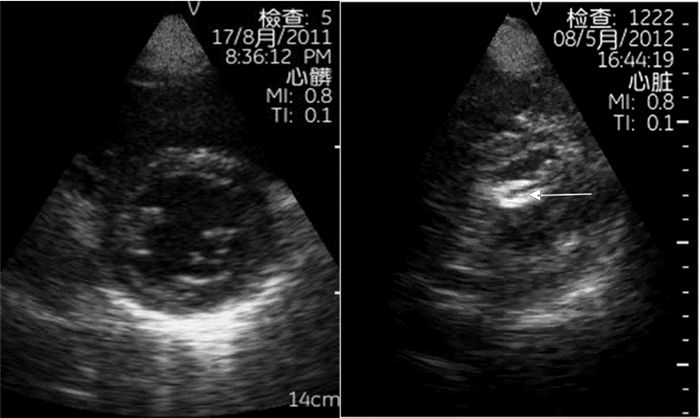

2.1.1 心包无回声区心包腔内出现无回声区(图 1),具体分级见表 1。伴有右心腔塌陷(特别是右室游离壁塌陷)、右房压力升高和/或心脏摆动(钟摆征)时,常见于心脏压塞。

| 图 1 心包积液(箭头示心包无回声区) |

室壁运动同步失调、运动幅度减低(收缩期室壁增厚率<30%,心内膜运动<5 cm)、消失(心内膜运动<2 cm)、矛盾运动及正常节段室壁运动幅度增强(图 2)。常见于缺血性心肌病、心肌梗死或心肌炎。

| 图 3 左心室高动力改变(左图为收缩期,右图为舒张期) |